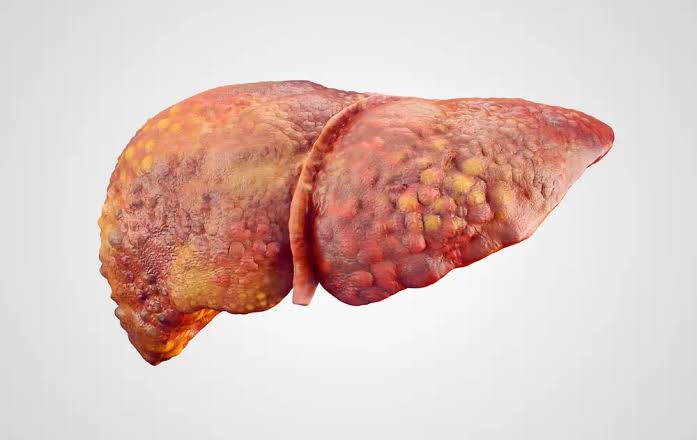

Child-Pugh Təsnifatı

12

2